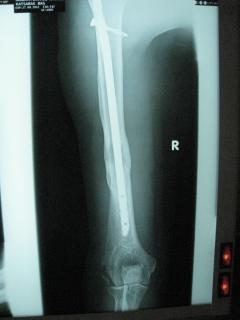

Περίπτωση 1ου ασθενούς

Με τα σύγχρονα μέσα που διαθέτουμε, όλα σχεδόν αυτά τα κατάγματα πρέπει να αντιμετωπίζονται χειρουργικώς. Υπάρχει πληθώρα υλικών οστεοσύνθεσης (πλάκες διαφόρων τύπων, ενδομυελικοί ήλοι, συστήματα εξωτερικής οστεοσύνθεσης) που είναι διαθέσιμα και επαφίεται στην εμπειρία του χειρουργού η επιλογή.

Οπως και άλλοι εξοικειωμένοι χειρουργοί διεθνώς, χρησιμοποιώ τεχνικές ελάχιστης παρέμβασης (Minimal Invasive Surgery), δηλαδή μικρές τομές, επειδή έτσι το χειρουργικό τραύμα είναι ελάχιστο, με αποτέλεσμα ταχύτερη επούλωση. Ταχύτερη πώρωση των καταγμάτων, ταχύτερη κινητοποίηση.